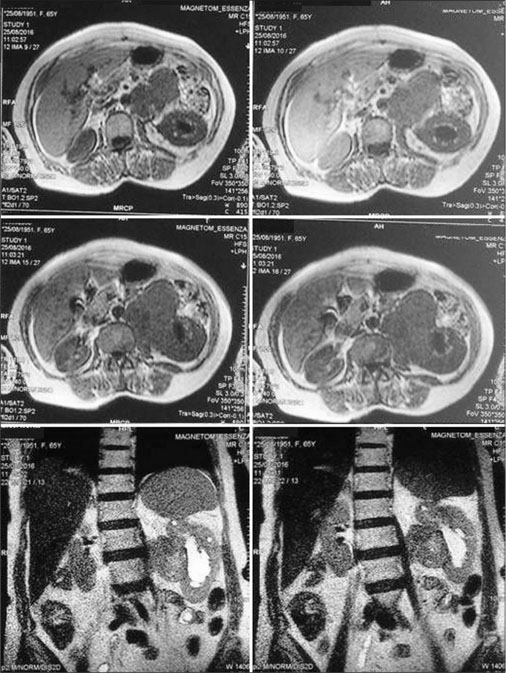

A 65-year-old female presented with off-and-on abdominal pain for the past 1 year. She was being treated symptomatically outside before reporting to the urology outpatient department of our hospital. There was no history of fever, weight loss, or nausea. Hematological investigations revealed a mild degree of anemia (hemoglobin 10.2 g%). Urine examination reported no abnormality. Serum electrolytes (sodium - 138 mEq/L and potassium - 4.0 mEq/L), urea (28 mg/dL), and serum creatinine (1.0 mg/dL) were within normal range. The ultrasound abdomen revealed left renal mass following which magnetic resonance imaging (MRI) abdomen was advised. MRI showed a left renal mass of 9.6 cm ? 5.4 cm ? 7.4 cm size, arising exophytically from the medial aspect in interpolar region, engulfing renal vein, and ureter with moderate hydronephrosis [Figure 1]. Left renal vein appeared retroaortic in position with loss of flow in proximal part and tumor thrombus in it without any extension into inferior vena cava. Imagings suggested a malignant renal mass likely renal cell carcinoma.

|?Figure. 1? Magnetic resonance imaging scans showing a left renal mass (9.6 cm ? 5.4 cm ? 7.4 cm) arising exophytically from the medial aspect in interpolar region, engulfing renal vein, and upper ureter